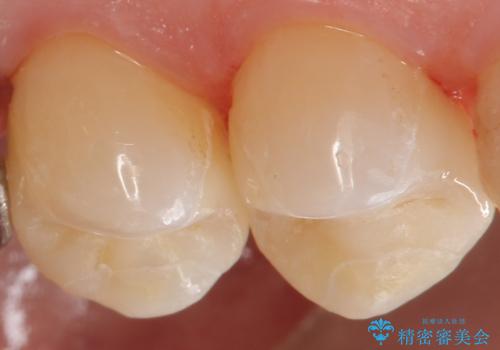

歯の内側に詰めるインレーでの修復でも、形によっては外から見える場合があります。

適合の良いセラミックインレーにやり替えることで外から見た時の違和感がなくなります。

また今回は治療前の写真で食べ物が詰まっている様子が伺えますが、適合がよく段差のない修復をすることで食べ物が詰まることを減らし、結果的に虫歯のリスクを下げることも期待できます。